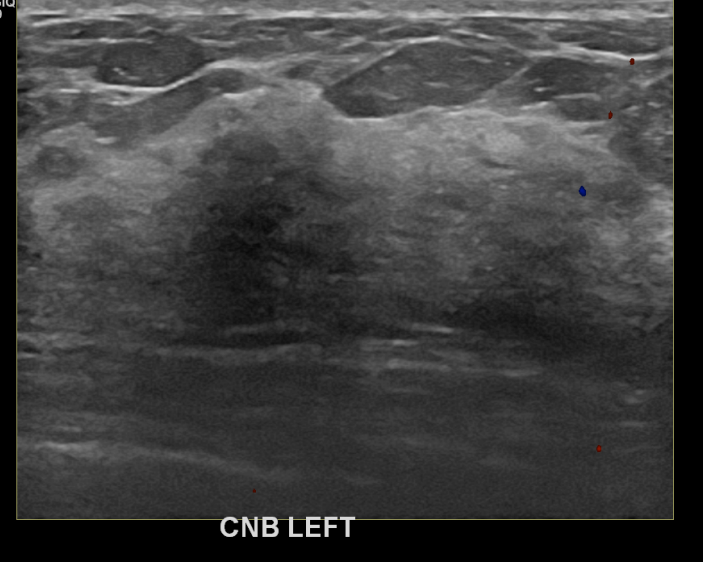

상기환자 건진상 이상소견으로 조직검사권유받고 내원하신 50대 여성분으로 좌측유방멍울  조직검사시행후 유방암 진단되었습니다.